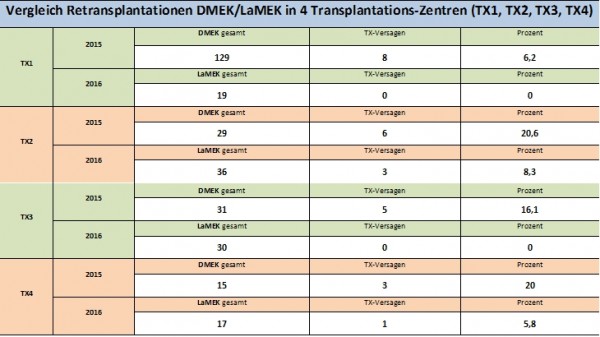

N. Hofmann, S. Wahl, M. Börgel, P. Szurmann: Pre-Cut LaMEK enables cell recovery through rest period before surgery. Vortrag auf dem XXXII Annual Meeting of the European Eye Bank Association, EEBA, 16-18 January 2020, Hannover

N. Hofmann, I. Wittmershaus, A.-K. Salz, J.-M. Blesin, N. Schwertner, M. Börgel: Globale Bedarfsanalyse – Angebot und Nachfrage nach Hornhauttransplantaten in Abhängigkeit der OP-Methode. Vortrag auf der 118. DOG (online), 08.-10.10.2020

A. Rickmann, S. Wahl, N. Hofmann, J. Knakowski, A. Haus, M. Börgel, P. Szurman: Comparison of preloaded grafts for Descemet membrane endothelial keratoplasty (DMEK) in a novel preloaded transport cartridge compared to conventional precut grafts. Cell Tissue Bank. 2020 Jun;21(2):205-213.